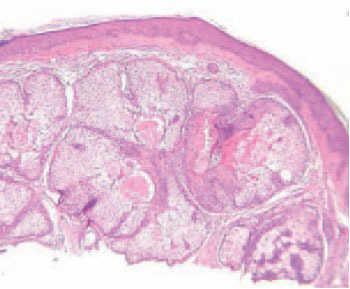

Fig. 3.—Imagen histológica. (Hematoxilinaeosina, ×40.)

El estudio histológico de una de las lesiones puso de manifiesto una epidermis adelgazada, ortoqueratósica y abundantes glándulas sebáceas normales en la dermis. Algunas de estas glándulas formaban parte de unidades pilosebáceas completas y otras no tenían folículos pilosos. Los conductos excretores estaban dilatados y ocupados en su mayoría por secreción sebácea. No se observaron signos de infección viral ni de malignidad, y se confirmó el diagnóstico clínico de hiperplasia de glándulas sebáceas.